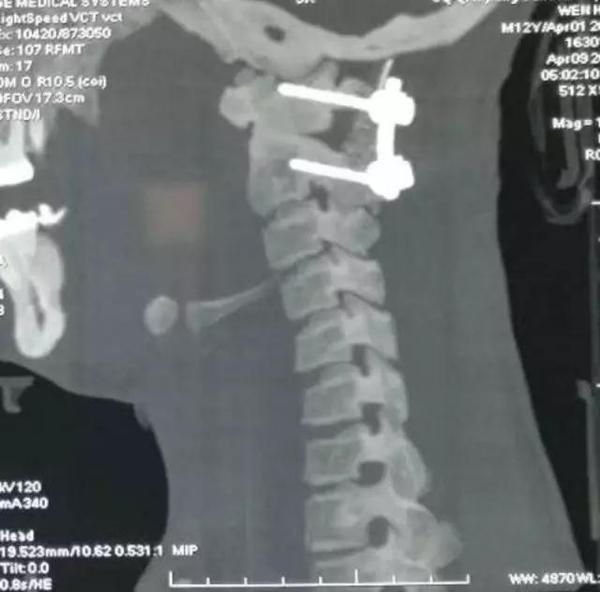

术前影像资料

2、颅颈畸形:寰枢椎半脱位,齿状突不连续

后路寰枢椎复位,C1-2融合术